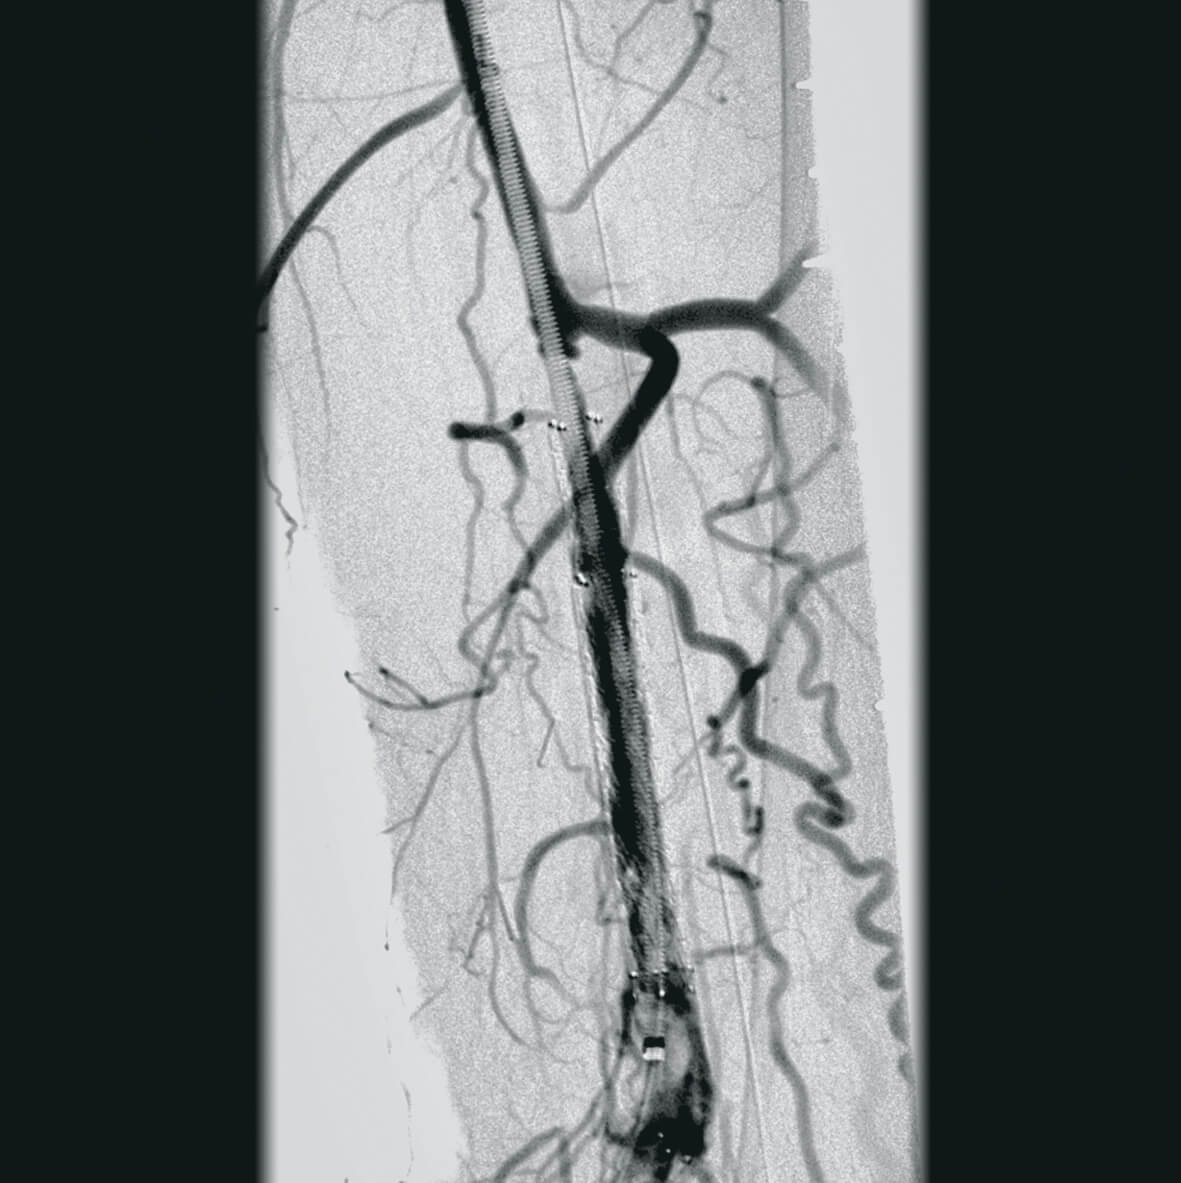

Полное отсутствие искажений снимков в сочетании с высоким динамическим диапазоном широко востребованы как при сложных операциях в нейрохирургии, сосудистой хирургии, инвазивной радиологии, так и в гибридных областях применения, а также в ортопедии, травматологии. В сосудистой хирургии особенно важны высокий динамический диапазон и пространственное разрешение, обеспечивающие детальную визуализацию даже мельчайших сосудов. Специализированное программное обеспечение SmartVascular позволяет проводить настройку системы для васкулярных операций и сосудистой хирургии.

- программный пакет для сосудистой хирургии,

- субтракционная ангиография с применением СО2.